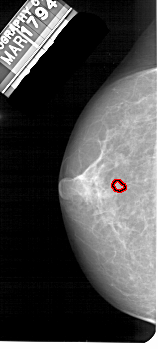

A_1545_1.LEFT_CC

LEFT_CC LINES 4876 PIXELS_PER_LINE 2206 BITS_PER_PIXEL 12 RESOLUTION 43.5 OVERLAY

FILE: A_1545_1.LEFT_CC.OVERLAY

TOTAL_ABNORMALITIES 1

ABNORMALITY 1

LESION_TYPE MASS SHAPE LOBULATED MARGINS OBSCURED

ASSESSMENT 4

SUBTLETY 2

PATHOLOGY BENIGN

TOTAL_OUTLINES 1